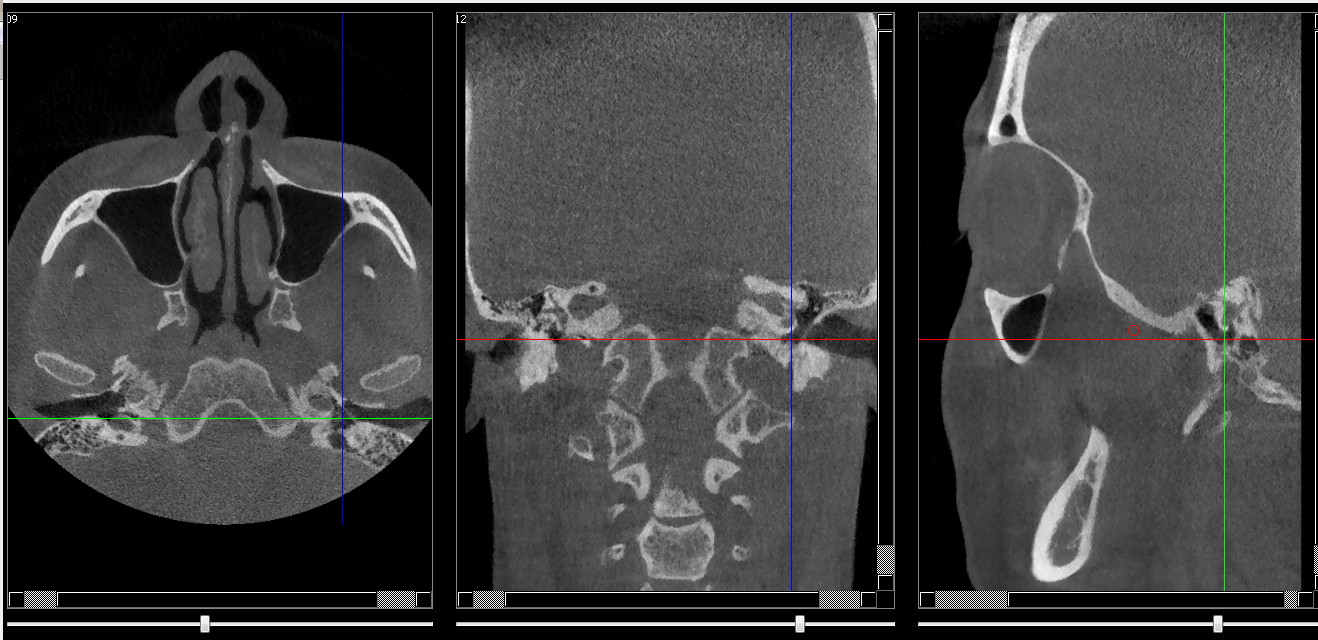

Structures osseuses

Repères anatomiques

- Coupe transversale

- Début : Partie inf de la grande aile du sphénoide

- Fin : Epine ded l'os sphénoide

- Coupe frontale

- Début : Cellules mastoides

- Fin : Clivus

- Coupe saggitale

- Début : Cochlea

- Fin : Méat acoustique externe